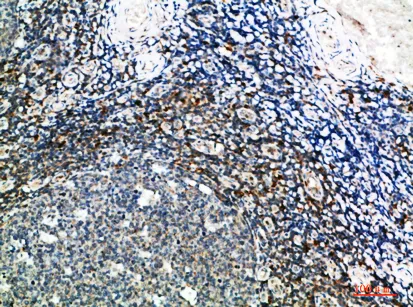

Inhibin α Rabbit Polyclonal Antibody

Cat: APRab12612

Size1:50μl Price1:$118

Size2:100μl Price2:$220

Size3:500μl Price3:$980

Size2:100μl Price2:$220

Size3:500μl Price3:$980